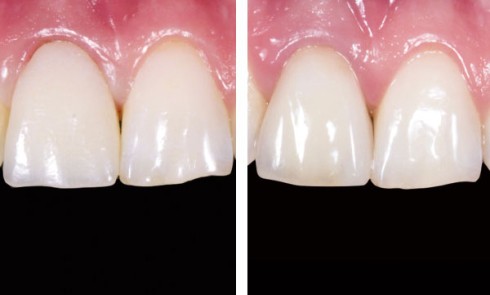

Article réservé à nos abonnés Utilisation du projet virtuel en odontologie dans une thérapeutique d’optimisation esthétique du sourire

Depuis plusieurs années, la demande esthétique des patients ne cesse de progresser. Dans nos sociétés modernes occidentales qui attachent beaucoup...